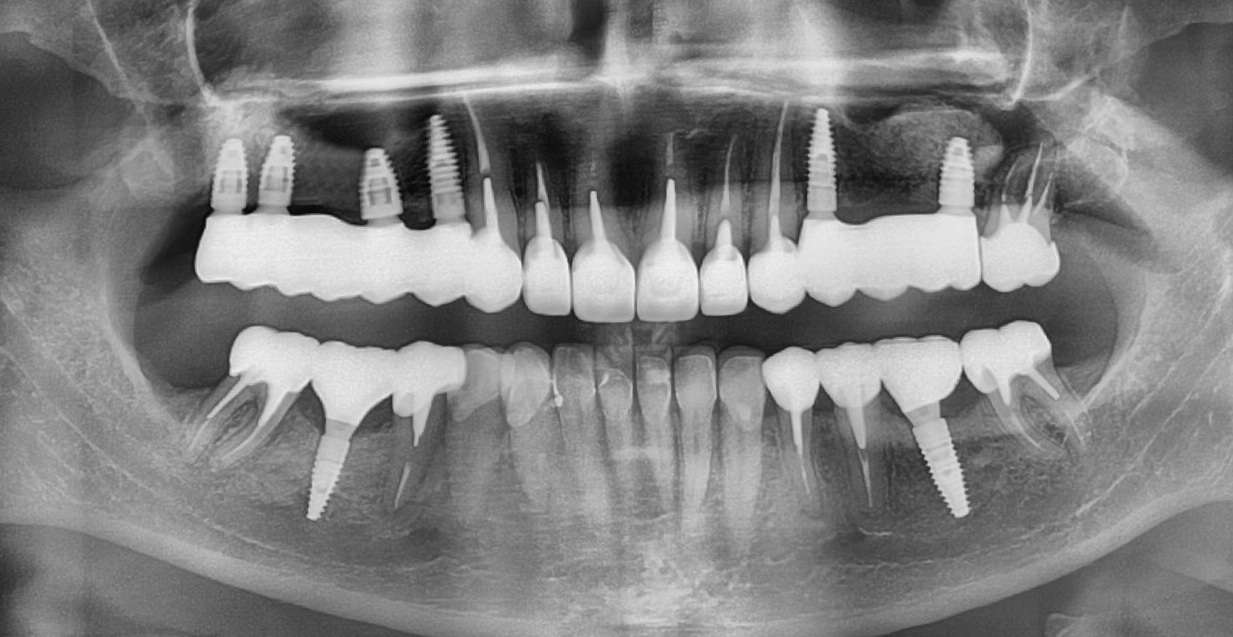

- провели зняття старих коронок, кісткові пластики, встановлення імплантантів;

І настала війна… Після 1,5 року ми зустрілись знову. А частини тимчасових зубів вже не було, але положення щелеп та імплантанти збереглись. Тому дуже швидко перевели роботу з тимчасових коронок на постійні. Загалом було встановлено всі види ортопедичних конструкцій: коронки, вініри та керамічні накладки.